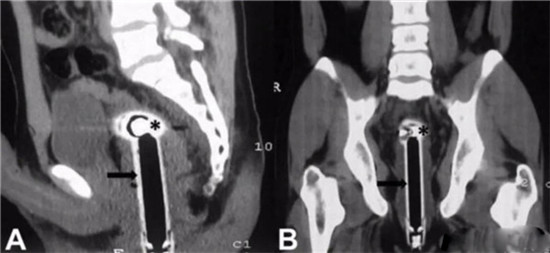

透视下从肛门里夹取直肠里的东西

一般情况下,这些肛门异物的病人,来到医院后,医生都会给他上麻醉。把病人麻醉后,在透视下从肛门里夹取直肠里的东西。

一般情况下,用产钳可以取出大部分直肠异物。

如果从肛门里取不出,那就要开膛破肚了。